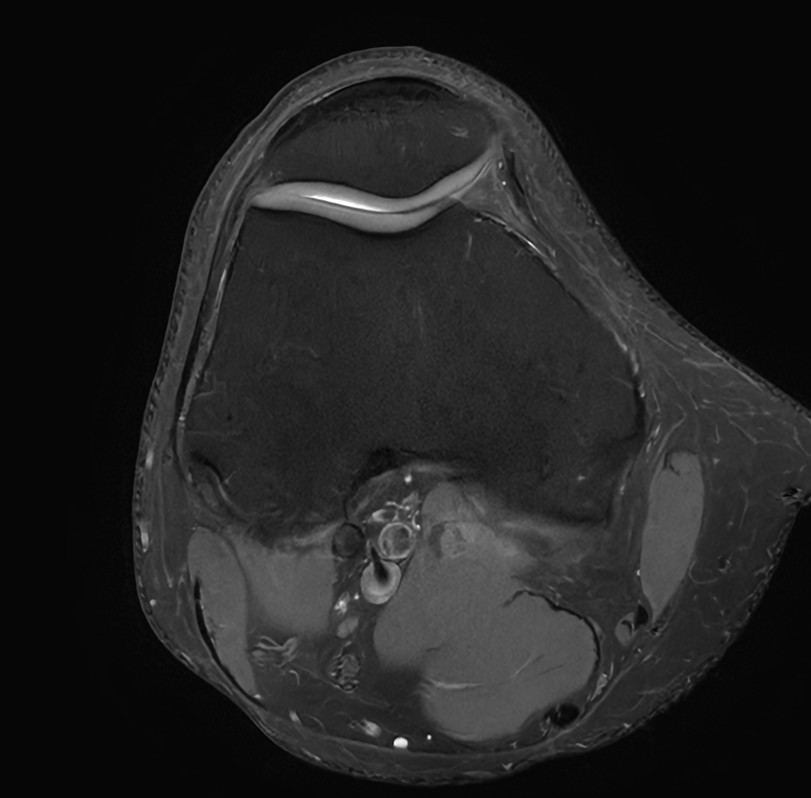

Fast Knee imaging with SmartSpeed Precise

• Clinical Application